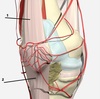

4

5

Perfectly

9

Q

8

A

vastus medialis

How well did you know this?

1

Not at all

2